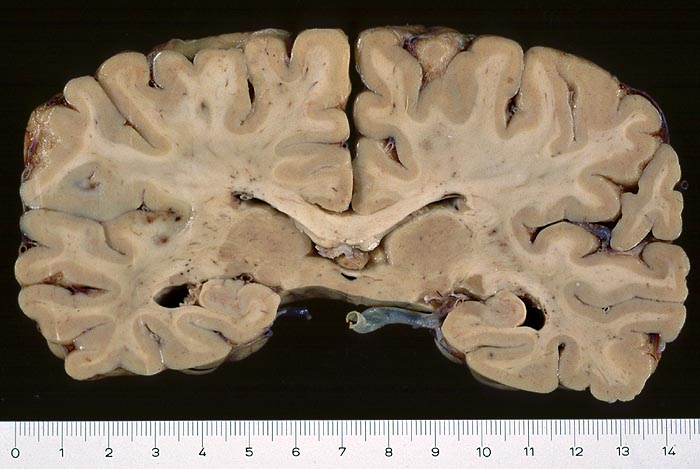

PathoPic ID 2943 - Septikopyämische Herde in der linken Inselrinde

Septikopyämische Herde in der linken Inselrinde

Entzündung infektiös

Hirn parietal

Nervensystem

Einzelne flohstichartige runde

hämorrhagische Herde in der linken Inselrinde.

Endokarditis

Makroskopie

75

männlich